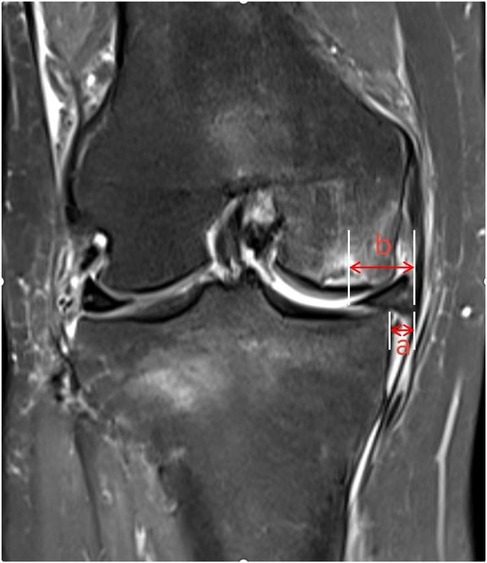

Meniscal extrusion (ME) refers to a pathological condition where the meniscal margin extends beyond the tibial plateau edge, resulting from the disruption of the internal circumferential collagen fiber structure that maintains hoop strength. In their review, Papalia GF et al. reported that ME is closely associated with articular cartilage wear and the development of OA, and may serve as a predictive risk factor and an imaging diagnostic marker for early-stage OA (18). The biomechanical dysfunction of the knee joint induced by ME (e.g., altered load distribution, reduced stability) accelerates the degradation of articular cartilage matrix, ultimately promoting the development of OA and SIFK (19). Shuhei Oda's team (20) conducted an MRI analysis of 108 SIFK patients and identified medial meniscal extrusion in 39 cases (36.1%), with the degree of extrusion positively correlated with SIFK severity. Based on these findings, the researchers proposed that medial meniscal extrusion is a critical pathogenic mechanism in the development and progression of SIFK. Furthermore, Hashimoto et al. suggested that when the relative extrusion percentage of the medial meniscus (i.e., the ratio of the extruded meniscal width beyond the tibial plateau edge to the total meniscal width, Figure 4) exceeds 33%, patients exhibit a significantly higher risk of disease progression (8). ME disrupts normal knee biomechanics, particularly by exacerbating stress concentration in the medial compartment, thereby playing a pivotal role in the multifactorial pathogenic cascade of SIFK involving “biomechanics-bone metabolism-microenvironment” interactions. In clinical practice, routine measurement of the relative extrusion percentage of the medial meniscus in SIFK patients—combined with comprehensive assessments including bone mineral density, symptomatology, and imaging staging—provides critical guidance for risk stratification and the formulation of individualized treatment plans.

Figure 4. The distance from the outer edge of the medial tibial plateau to the outer edge of the medial meniscus is measured on the image, with the measured meniscal protrusion value denoted as “a”. The absolute value of medial meniscal protrusion is denoted as “b”. The relative protrusion rate of the medial meniscus is calculated as a/b × 100%.